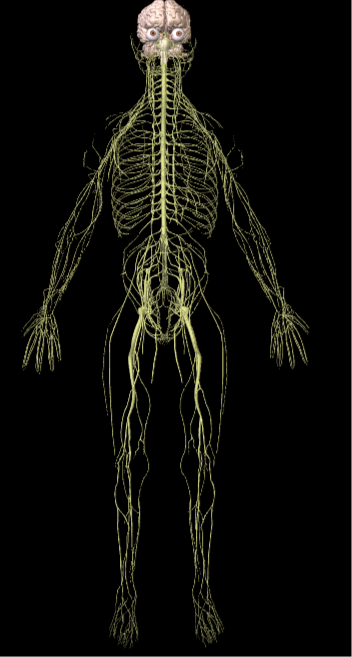

Hasta hace poco, se veía el sistema nervioso periférico como meros cables de unión que transportaban información. Hoy en día, lo vemos como tejido vivo: Si lo cortamos, no se va el dolor, paradógicamente, la sensibilidad a veces se exacerba, a veces. Desafortunadamente esta información ha llegado demasiado tarde para las neurotomías realizadas en los 60 y 70s. Incluso en las simpactectomías, las fibras aferentes pueden desarrollar sensibilidad a la adrenalina.

La próxima vez que veas ballet, cualquier deportista o contorsionista, imagínate las demandas físicas del sistema nervioso y maravíllate con su adaptabilidad de moverse, doblarse y estirarse. Este concepto de la biomecánica del sistema nervioso, o como Michael Shacklock denominó en 1995, "neurodinamica", es un concepto relativamente nuevo. Neurodinamia es algo más que ejercer tensión, es un concepto que nos ayuda a unir conceptos meramente mecánicos a términos fisiológicos de plasticidad neural. El objetivo del tejido neural es lograr que haya una comunicación óptima en todas las situaciones. Ahora, se sabe más sobre la complejidad de esta comunicación electroquímica en una estructura que es sensitiva, reactiva y plástica, que está contínuamente doblándose, estirándose y adaptándose. El tejido conectivo del sistema nervioso, envuelve a las neuronas y la glia para brindar protección a la misma, tanto de sustancias químicas como de fuerzas indeseadas. Ese tejido conectivo, está conectado desde el craneo, columna vertebral, filum terminale y la cobertura de los nervios periféricos. El tejido conectivo tiene conexiones con otros tejidos (Butler, The Sensitive Nervous System), que pueden explicar por qué el dolor de cabeza puede estar relacionado con el coxis:

Los libros de texto, nos han dividido el sistema nervioso en sistema periférico, central y autonómico. Una vez divididos así, puede ser dificil ponerlos juntos de nuevo, pero todas las funciones del sistema nervioso dependen unas de otras. La conexión eléctrica, mecánica y química del sistema nervioso es indivisible, un cambio en una parte del sistema, afecta a las otras partes. A veces, una extensión cervical, relaja el dolor de la pierna.